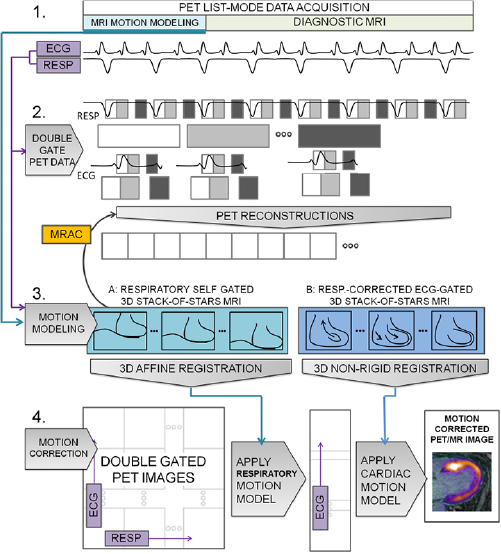

The overall approach to motion correction taken here is described in figure 1. The RTA approach (Picard and Thompson 1997, Klein et al 1997) is centered on three components: (1) Measure the physiological phase of respiratory and cardiac motion at all times during the acquisition of PET data. (2) Bin all PET data into distinct cardio-respiratory phases. Thus, for N respiratory phases and M cardiac phases, there are N × M distinct bins of data. Binned data is then reconstructed to form an image for each physiological phase. (3) Model the physiological motion between each of the phases and a single reference phase. Motion vector fields (MVFs) describing the transformations between phases can then be applied to the individually reconstructed PET images to form a single MC image at the reference phase. To study the feasibility of MC PET/MR, the RTA method was initially selected due to the simpler implementation of the methodology compared to more sophisticated approaches that incorporate MVFs into the iterative PET reconstruction (Qiao et al 2006, Li et al 2006, Lamare et al 2007, Karakatsanis et al 2016). These latter methods are known to have more optimal noise characteristics (Polycarpou et al 2012, Fayad et al 2015) however they may also be prone to distributing errors in MVFs throughout the data.

Figure 1. The method for RTA motion correction. In step 1, list-mode PET data are acquired simultaneously with MR image-based motion modeling, and diagnostic MR image data. Physiological phase is also monitored throughout. In step 2, PET data are double-gated using the acquired physiological phase information, first into respiratory bins; subsequently, each respiratory bin is divided further into bins according to cardiac phase resulting in N (respiratory) × M (cardiac) phase bins. PET images for each bin are then reconstructed. MR-based attenuation correction (MRAC) data are derived from the motion modeling image data. The appropriate respiratory motion models from step 3 are applied to the MRAC data for the PET reconstruction for each respective bin. In step 3, MVF models are calculated. Using the physiological phase information to analogously gate MR data, images representing respiratory and cardiac phases are produced. Affine and non-rigid registration is applied to subsequent physiological phase images to estimate MVFs for respiratory and cardiac motion models, respectively. In step 4, the NxM double-gated PET images are first spatially transformed by the appropriate respiratory and cardiac transforms into a single reference frame. Then, they are averaged in the final step to produce a motion-corrected PET/MR image.